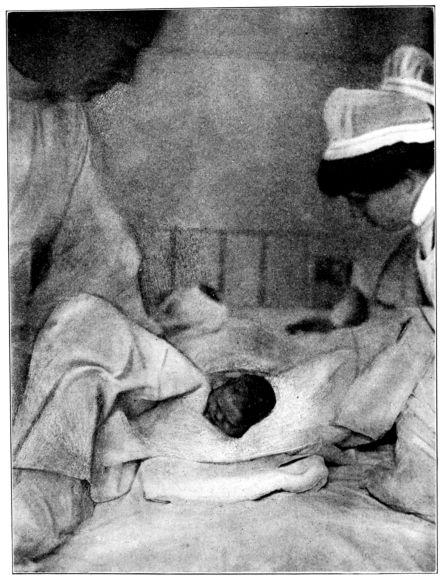

| 154. | Bathing the baby | 467 |